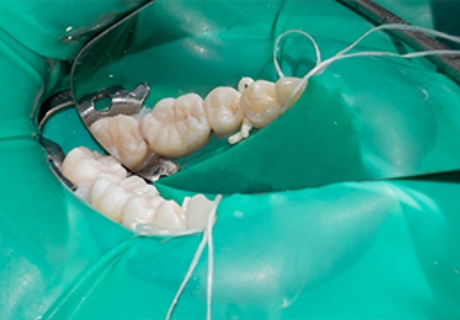

非常に難しく、技術が必要な根管治療にはなりますが、当院ではそんな繊細な根管治療を可能にするため、マイクロスコープやラバーダムを使用しております。

ラバーダムの装着で細菌の流入を防止

ラバーダムとは、歯に装着するゴム状のコートで、根管内に細菌が入り込むリスクを抑えるために使用しています。

治療中に細菌が入り込んでしまうと、再治療が必要になったり、気づかず放置しておくと知らないうちにむし歯が広がっていることもしばしば。

それを防ぐために、当院ではラバーダムを使用して根管治療を行っています。

一度の治療でより確実な治療を行うために、このラバーダムは必要不可欠なのです。